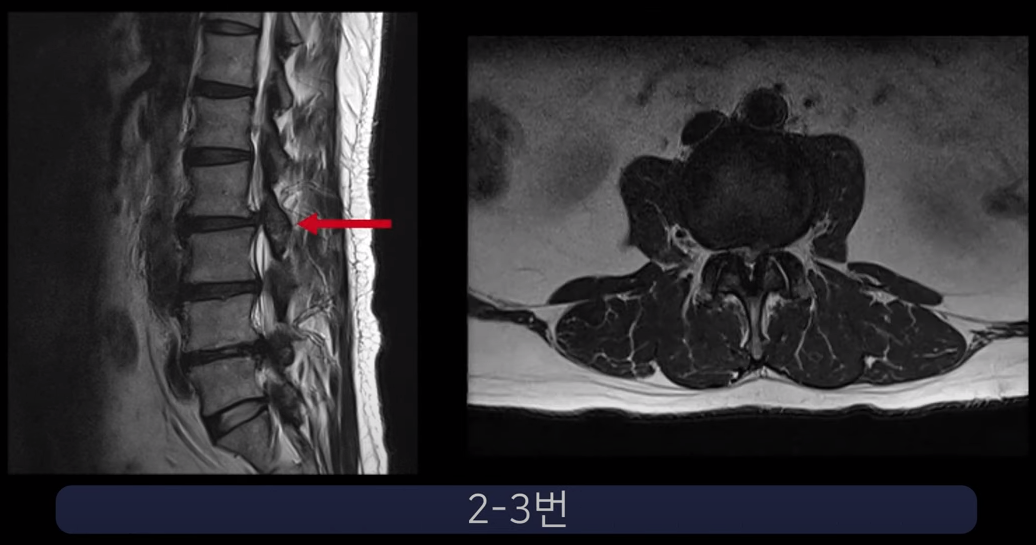

실제 척추관과 추간공이 심하게 막힌 두 환자 케이스를 보여드리겠습니다.

첫 번째 환자분입니다. 이 환자분은 허리 세 마디에 심한 협착이 있습니다. 2-3번, 3-4번, 4-5번 이렇게 척추관이 세 마디가 심하게 막혀있습니다.

25년간 허리에 신경주사를 맞아왔는데 이젠 효과가 전혀 없고, 작년부터 거의 걷지 못하는 상태가 되어 수술을 결심하였습니다. 대학병원에서 수술이 어렵다고 했고 유명 척추병원에서 3주에 걸쳐 3번의 수술을 권했습니다.